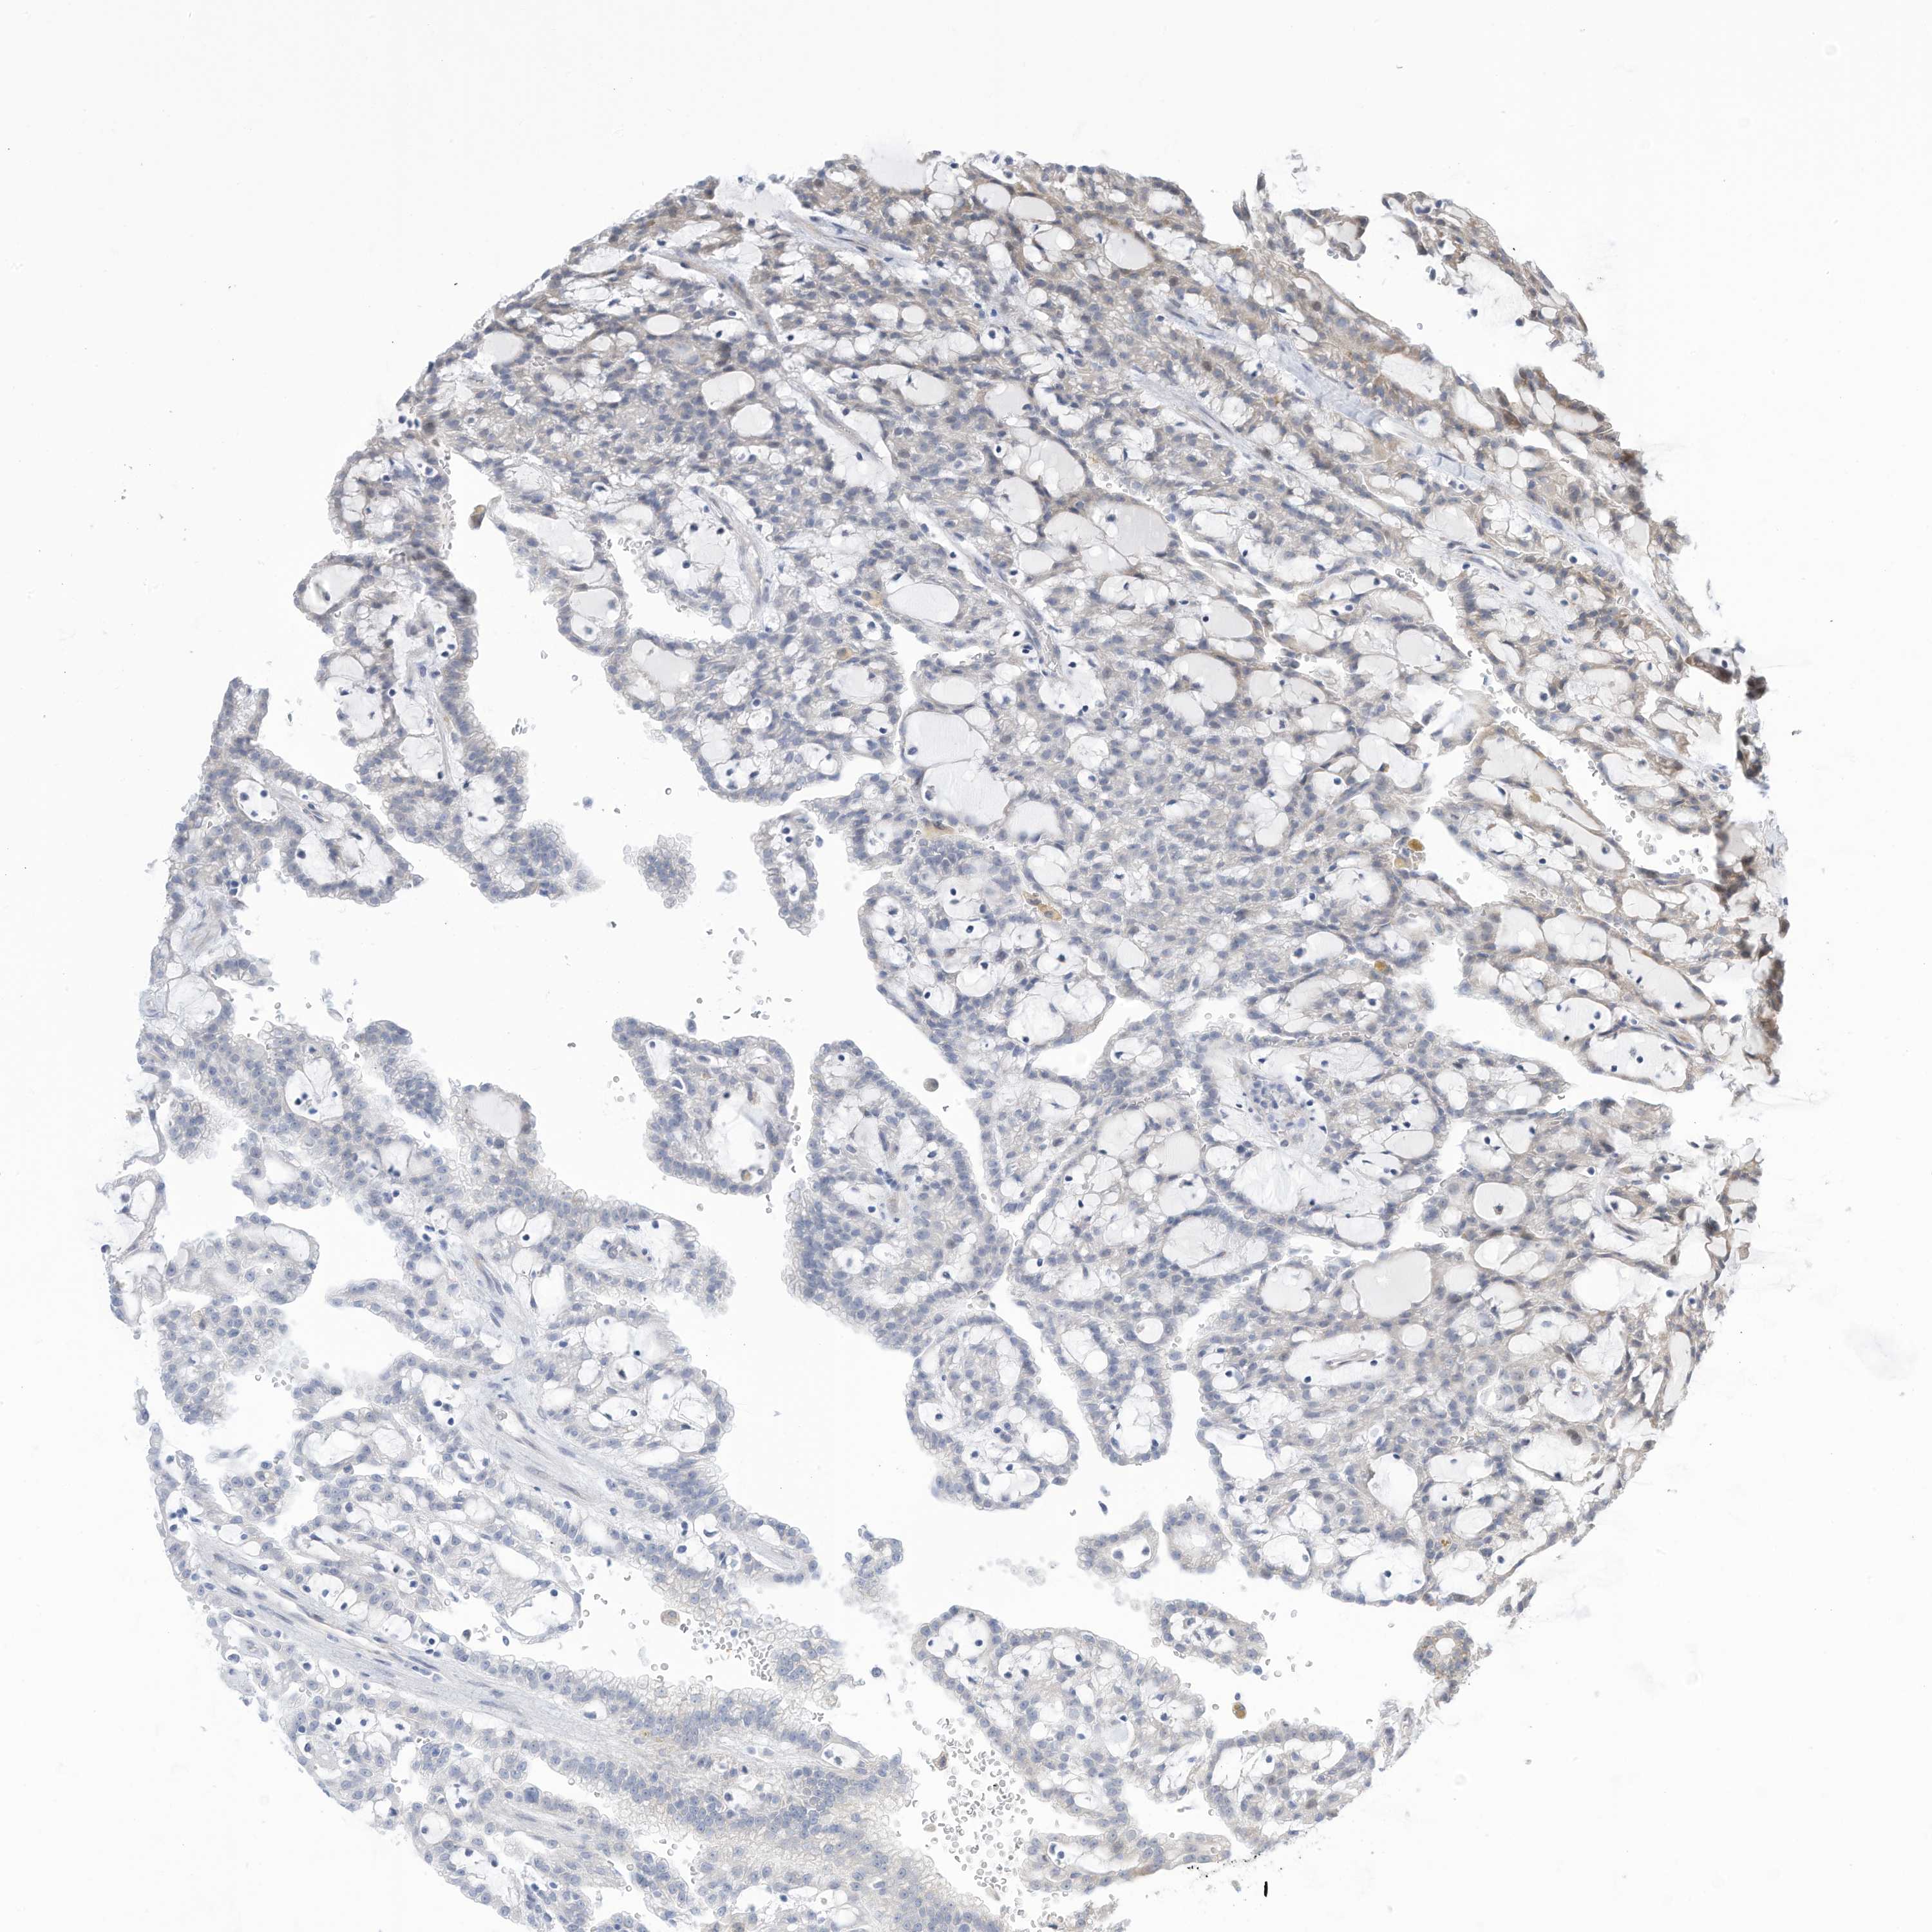

KIDNEY RENAL CLEAR CELL CARCINOMA (VALIDATION) - Interactive survival scatter ploti

The Survival Scatter plot shows the clinical status (i.e. dead or alive) for all individuals in the patient cohort, based on the same data that underlies the corresponding Kaplan-Meier plots. Patients that are alive at last time for follow-up are shown in blue and patients who have died during the study are shown in red.

The x-axis shows the expression levels (FPKM) of the investigated gene in the tumor tissue at the time of diagnosis. The y-axis shows the follow-up time after diagnosis (years). Both axes are complimented with kernel density curves demonstrating the data density over the axes. The top density plot shows the expression levels (FPKM) distribution among dead (red) and alive patients (blue). The right density plot shows the data density of the survived years of dead patients with high and low expression levels respectively, stratified using the cutoff indicated by the vertical dashed line through the Survival Scatter plot. This cutoff is automatically defined based on the FPKM cutoff that minimizes the p-score. The cutoff can be changed by dragging the vertical line or by entering a cutoff value in the square labeled "Current cut-off".

Under the Survival Scatter plot the p-score landscape (black curve; left axis) is shown together with dead median separation (red curve; right axis). Dead median separation is the difference in median mRNA expression between patients who have died with high and low expression, respectively. It is calculated as follows: median FPKM expression of dead patients with high expression - median FPKM expression of dead patients with low expression. This is intended to aid the user in visually exploring custom cutoffs and the associated p-scores and dead median separation.

Individual patient data is displayed and can be filtered by clicking on one or more of the category buttons on the top of the page. Categories describing expression level and patient information include: high, low, alive, dead, female, male and tumor stages. The scale of the x-axis can be toggled between linear and log-scale by clicking on the "x log" button. Mouse-over function shows TCGA ID, patient information and mRNA expression (FPKM) for each patient.

& Survival analysisi

Kaplan-Meier plots summarize results from analysis of correlation between mRNA expression level and patient survival. Patients were divided based on level of expression into one of the two groups "low" (under cut off) or "high" (over cut off). X-axis shows time for survival (years) and y-axis shows the probability of survival, where 1.0 corresponds to 100 percent.

ZNF292 is validated prognostic, high expression is favorable in Kidney Renal Clear Cell Carcinoma (validation)

: 12.28

Average pTPM 14.4

Number of samples 100